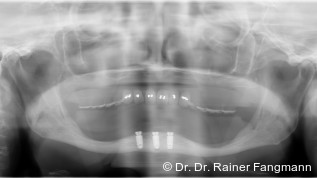

Eine kürzlich veröffentlichte Studie der Universität Göteborg bestätigt die Langlebigkeit von Zahnimplantaten. Dafür untersuchten die Forscher eine kleine Gruppe von Patienten, die zwischen 1982 und 1985 Einzelzahnimplantate erhalten hatten. Fast 40 Jahre später sind diese Implantate noch immer funktionstüchtig und stabil. Von den ursprünglich 16 Studienteilnehmern nahmen 13 an der Nachuntersuchung teil. Die Ergebnisse zeigen, dass alle 18 analysierten Implantate kaum Knochenverlust aufwiesen und fest im Kiefer verankert blieben.

Veröffentlicht wurde die Studie in der Fachzeitschrift "Clinical Implant Dentistry and Related Research" (doi:10.1111/cid.13443). Sie gilt als die weltweit längste Nachbeobachtungsstudie zu Einzelzahnimplantaten. Neben der mechanischen Stabilität der Implantate konnte auch eine gute biologische Integration festgestellt werden. Der geringe Knochenverlust, der über die Jahre dokumentiert wurde, bestätigt, dass die Osseointegration auch langfristig zuverlässig funktioniert. Das unterstreicht die Bedeutung einer sorgfältigen Planung und regelmäßigen Nachsorge für den langfristigen Erfolg von Implantaten.

Die Untersuchung zeigt zudem, dass die Implantate selbst zwar langlebig sind, die darauf befestigten Kronen jedoch eine kürzere Lebensdauer haben. Nach 40 Jahren waren nur noch etwa 60 % der ursprünglichen Kronen vorhanden, da viele im Laufe der Zeit aus ästhetischen Gründen ersetzt wurden. Jan Kowar, Prothetiker und Mitautor der Studie, sieht in der Weiterentwicklung neuer Kronenmaterialien eine Möglichkeit, Implantatbehandlungen zukünftig noch langlebiger zu machen.